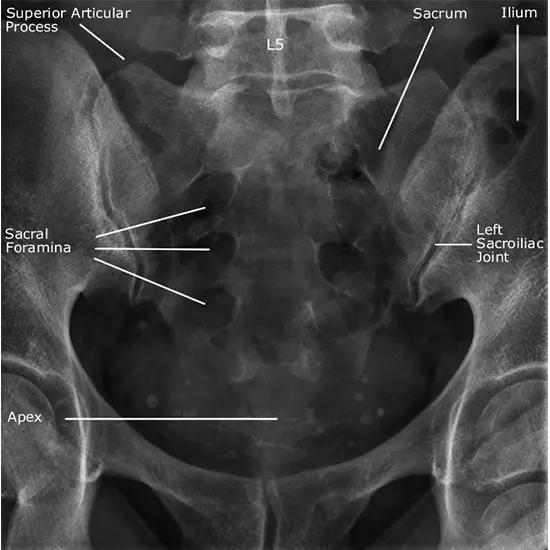

What is an X-ray Lumbar Sacral Ap & Lat View Test?

This imaging exam provides your doctor with a visual representation of the structure of your lower back.